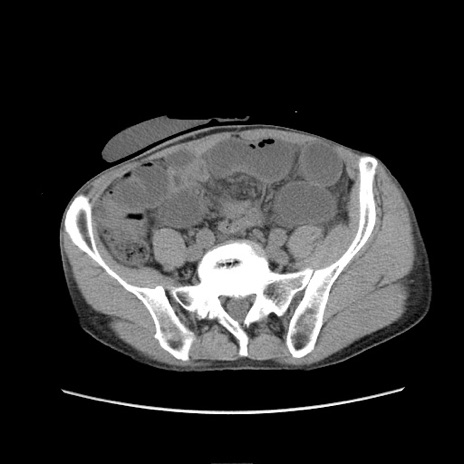

冠状断像

症例11(横断像)

【症例】 60歳代男性

【主訴】 下腹部痛

【現病歴】 本日夜中より下腹部痛の症状認め、受診。

【既往歴】 膀胱癌(膀胱全摘+尿管皮膚瘻術) 、胃癌術後

【身体所見】 BT 35.3℃、PR 58/min、BP 136/98mHg、腹部平坦、軟、腸蠕動音±、ストマ留置あり、左上腹部~正中部に圧痛あり、反跳痛なし。

【データ】WBC 5100、CRP0.01